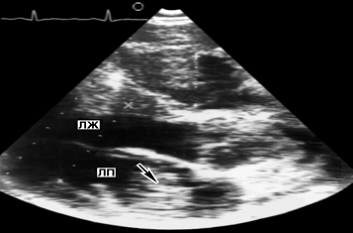

Рис. 24а). Эхокардиограмма больного с экссудативным перикардитом: двухмерная эхокардиограмма в проекции длинной оси (эхонегативные полости представлены темными, а эхопозитивные структуры - светлыми полями); хорошо определяется эхонегативное пространство (указано стрелками), за задней стенкой левого желудочка - полость перикарда, заполненная выпотом

Рис. 1. Схема основных доступов для ультразвукового исследования сердца в сечении длинной оси (а), короткой оси (б) и с обозрением четырех камер сердца (в): 1 - парастернальная позиция датчика, место локации в III-IV межреберьях слева от грудины; 2 - верхушечная позиция, место локации в IV-V межреберьях по левой среднеключичной линии; 3 - супрастернальная позиция, локация со стороны яремной ямки; 4 - субкостальная позиция, локация со стороны эпигастральной области. Исследуемые структуры сердца на этом и других рисунках к статье имеют обозначения: АО - аорта, ЛЖ - полость левого желудочка, ЛП - полость левого предсердия, ПЖ - полость правого желудочка, ПП - полость правого предсердия